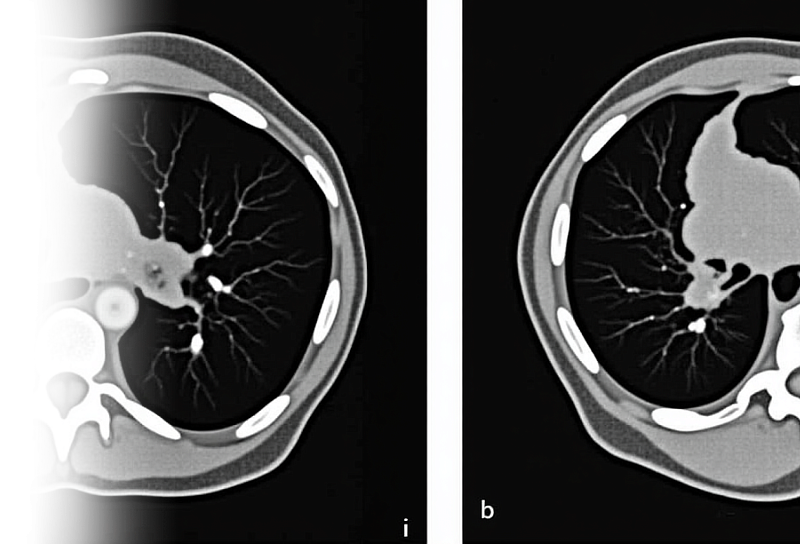

Компьютерная томография органов грудной клетки – важный метод исследования паренхимы легких, органов средостения, костного каркаса грудной клетки и мягких тканей.

Как проводится КТ органов грудной клетки?

Пациент ложится на стол сканера, который постепенно перемещается в аппарат. Во время сканирования следует лежать неподвижно, чтобы получаемые трехмерные изображения были четкими и неискаженными.